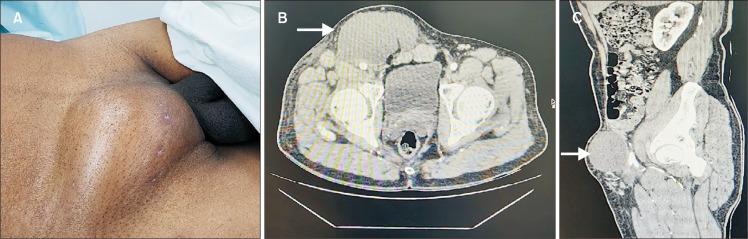

钝性创伤致腹股沟淋巴管瘤——一种罕见并发症及处理考量:病例报告

Lymphoceles are common complications after certain surgical procedures. Blunt trauma can occasionally result in similar lymph accumulation. Herein, we present the rare case of a patient who developed a lymphocele in his right groin following a blunt trauma from a fallen tree branch. Aspiration and sclerotherapy were unsuccessful, and the lesion ultimately required surgical excision. Lymphoceles should be considered a rare differential diagnosis for post-traumatic cystic swelling, and their management should follow similar guidelines to those used for post-surgical lymphocele management.

淋巴管瘤是某些外科手术后常见的并发症。钝性创伤偶尔也会导致类似的淋巴液积聚。在此,我们报告一例罕见病例,一名患者因被倒下的树枝钝性创伤后,右侧腹股沟出现淋巴管瘤。抽吸和硬化治疗均未成功,病变最终需要手术切除。对于创伤后囊性肿胀,应将淋巴管瘤视为一种罕见的鉴别诊断,其治疗应遵循与手术后淋巴管瘤治疗相似的指导原则。